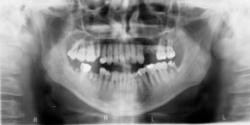

Viaceré klinické štúdie jednoznačne preukázali zvýšenie terapeutického efektu chirurgických zákrokov pri použití doštičkového koncentrátu. Sú prínosom pre pacienta z hľadiska skrátenia doby hojenia a práceneschopnosti, miernejších pooperačných komplikácií. Použitie PRP výrazné zlepšuje subjektívny pooperačný stav pacienta (menší opuch, menšie bolesti), urýchľuje hojenie mäkkých tkanív a tvorbu nového kostného tkaniva. Pomocou RTG diagnostiky boli posudzované kostné štepy ako zrelšie v porovnaní s reálnou dĺžkou hojenia, čo umožňuje včasnú funkciu a možnosť skoršieho zaťaženia.